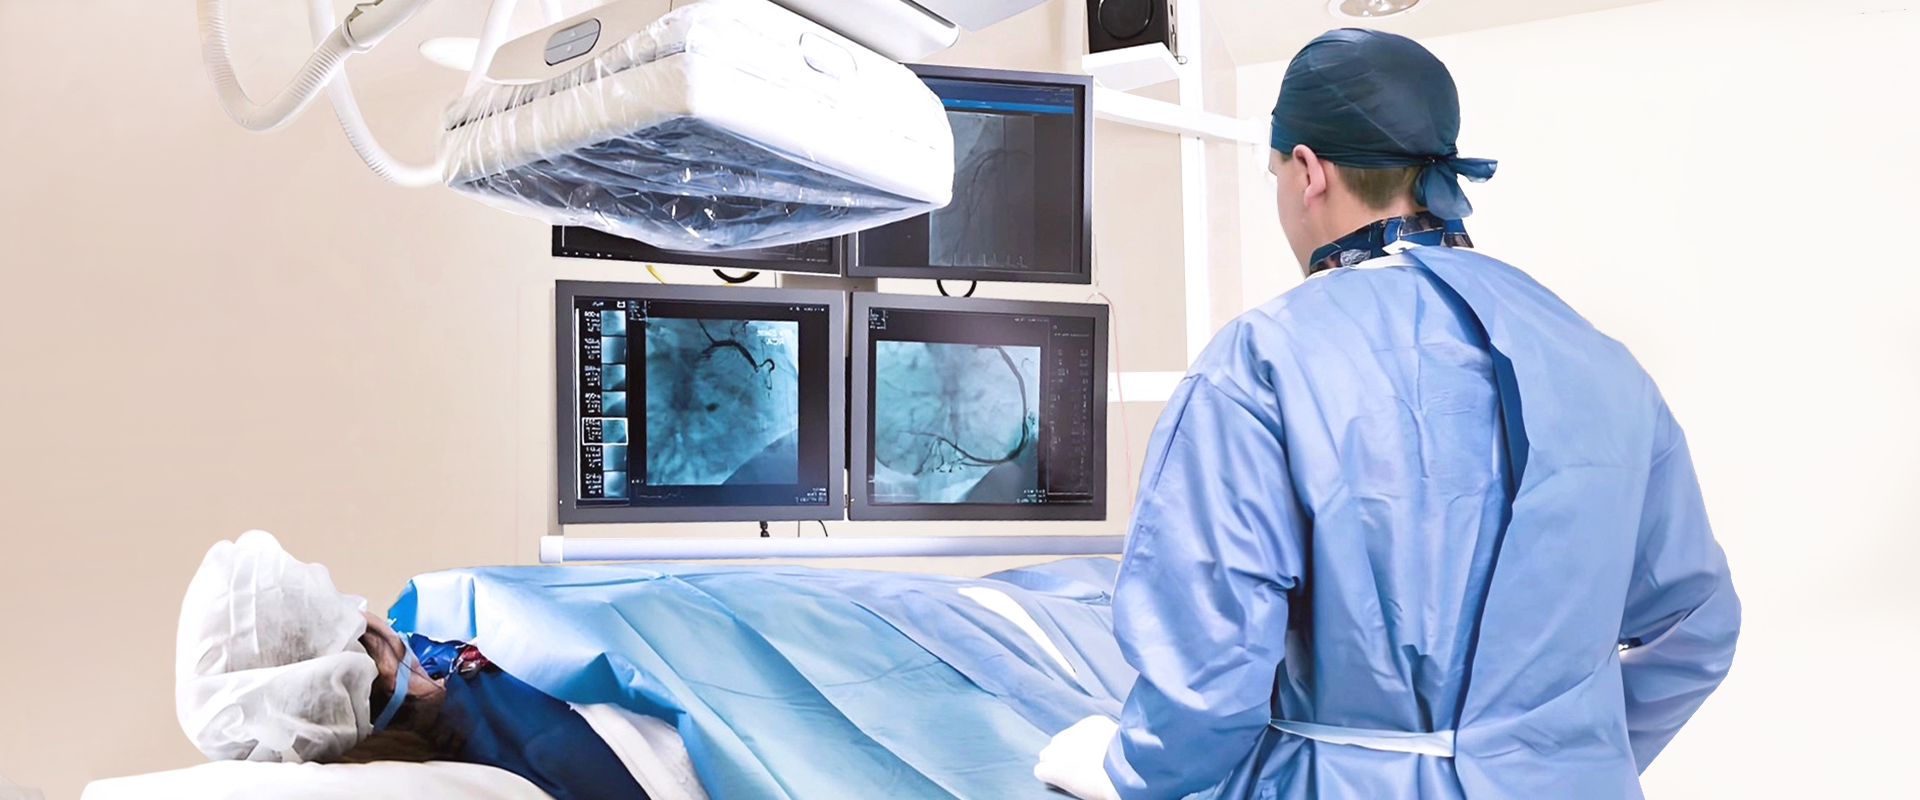

PCI Solution

Lepu Medical leverages cutting-edge technologies and high-performance consumables to deliver comprehensive, full-process vascular intervention solutions. For coronary calcification lesions, Lepu provides a step-by-step device solution portfolio, addressing various types and complexities of calcified lesions, and empowering clinicians with tailored tools for optimal patient outcomes.In the peripheral vascular field, Lepu offers integrated support from diagnosis to treatment, enabling safer, more efficient, and minimally invasive procedures.Through continuous innovation and deep clinical insight, Lepu Medical is committed to advancing vascular reconstruction across both peripheral and coronary domains.

Coronary Calcification Lesion Treatment Solution

Lepu Medical is deeply engaged in the field of cardiovascular intervention, providing comprehensive and step-by-step device solutions for different types of coronary calcification lesions.

Peripheral Solutions

With innovative technologies and high-end consumables as the core, Lepu Medical provide full-process support from diagnosis to treatment, helping clinicians achieve safer, more efficient and more minimally invasive peripheral vascular reconstruction.